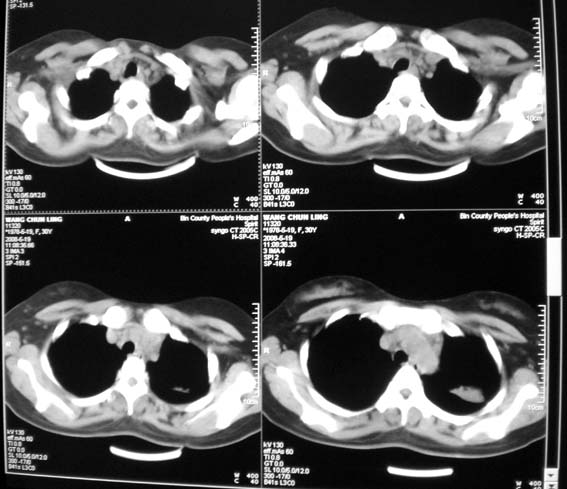

女,30岁,怀孕后3个月,拍片时肺结核,抗结核治疗4个月复查。

前段支气管通畅,但尖后段支气管闭塞,建议支纤镜除外肺癌,有原片吗,对比一下了。

结核.前段支气管通畅,但尖后段支气管闭塞,建议支纤镜除外肺癌

纵隔淋巴结肿大,见意出外占位